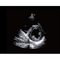

Аппарат УЗИ Chison QBit 7

Аппарат УЗИ Chison QBit 7 отличается компактными размерами и имеет небольшой вес, за счет чего его легко перемещать с места на место при необходимости. В конструкции модели предусмотрена клавиатура с подсветкой. Для удобства ее можно регулировать по высоте и повороту. На клавиатуре есть два USB-порта, к которым подключаются флеш-накопители.

УЗИ-сканер экспертного уровня предназначен для исследований в разных медицинских областях. Система выдает четкие, контрастные и детализированные изображения внутренних органов, что помогает врачам ставить точные диагнозы. Может использоваться в клиниках, педиатрических центрах, кабинетах УЗИ, стационарных отделениях.

· 19-дюймовый цветной ЖК-монитор с немерцающим дисплеем;

· Функция «Суперзум» для увеличения изображения на весь экран;